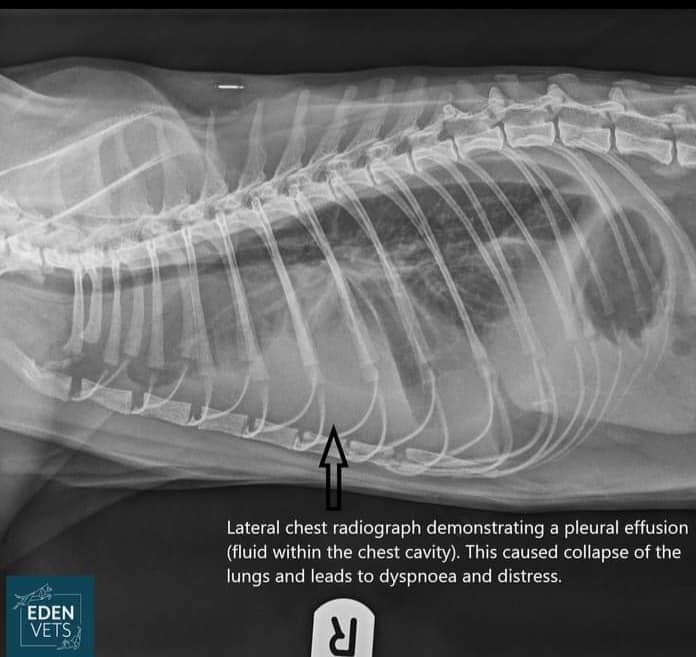

Dave is 3 years old, he was adopted from us as a kitten by the wonderful Pat, who is currently making beautiful cat beds and other goodies for us to sell to raise funds. Being the kind of owner who knows her cats inside out, Pat noticed one evening that Dave was very out of sorts; his breathing was very fast and laboured and he was quite obviously in a lot of distress. Pat took him along to Eden Vets in Shavington (out of hours, as emergencies often are!) where, after stabilizing him with oxygen,fluids and antibiotics, blood tests and scans found he had sepsis, fluid and pus in his chest cavity and collapsed lungs... Dave was very, very sick indeed. Thanks to the skill of the vets and nurses at Eden, after a week of intensive care Dave was on the mend and on his way home... a fantastic result, well done Eden Vets!

Click to see a larger image